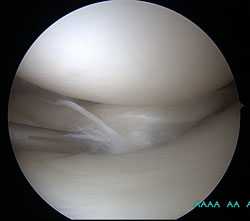

Дегенеративный комбинированный разрыв тела и заднего рога внутреннего мениска коленного сустава.

Продольный разрыв заднего рога наружного мениска, сопровождающийся его гипермобильностью. При таком разрыве мениск может значительно смещаться внутрь сустава создавая ощущение механического блока, инородного тела, нестабильности в суставе, заклинивания, щелчков.